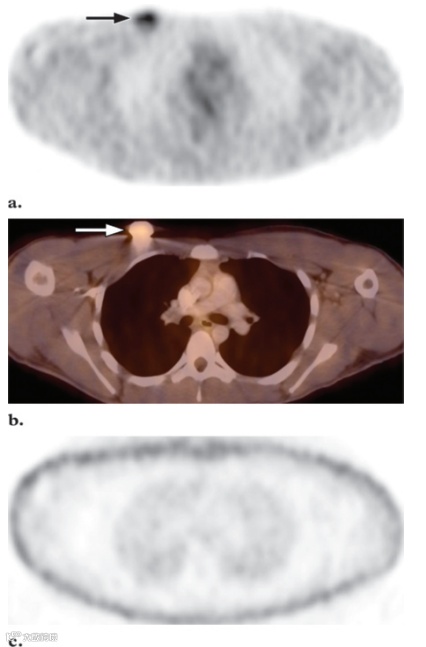

使用组合式PET/CT成像系统会产生在专用PET系统上看不到的独特伪影。最常见的伪影与使用CT数据而非PET数据进行衰减校正有关。假体、起搏器或化疗导管等金属物体可能会导致伪影活动增加并导致假阳性结果(图20)。高CT衰减值(以亨斯菲尔德单位表示)会导致PET衰减系数错误地偏高,从而导致高估衰减校正图像上与金属物体相对应的PET活性。同样,高浓度的静脉和口服造影剂、增强后CT数据用于衰减校正,可能会导致PET活动过度校正和假阳性结果。过度浓缩的静脉造影剂通常出现在静脉导管近端区域(例如肘前注射后的上臂和腋窝)。过度浓缩的口服造影剂通常表示最近一次荧光透视或CT检查后结肠中残留的钡。查看未衰减校正的PET图像有助于区分这种衰减校正伪影与真正的代谢亢进,因为这种伪影的高活性不会出现在未校正的图像上。口服造影剂可能不会显著影响图像质量和视觉解释。然而,标准化摄取值 (SUV) 等半定量指标可能会受到轻微影响。静脉造影剂还可能导致对PET衰减因子的估计过高,以及造影剂高度浓缩区域的SUV增加。然而,这种增加可能在临床上并不显著,PET/CT静脉增强CT可与PET联合用于评估癌症患者。由于儿童时期身体的变化和生长,计算儿童SUV的最佳方法可能与成人不同。因此,有人建议,对于儿童患者,以体表面积计算的SUV可以作为更好的代谢活动,该方法比根据体重计算的SUV更有效,并且可能是最适合对这些患者进行随访的方法(假设要使用SUV)。

图20. 衰减校正伪影。

(a)横向衰减校正FDG PET扫描显示右上胸壁的摄取增加灶(箭头)。

(b)横向融合PET/CT图像也显示摄取增加灶(箭头),该发现代表导管。

(c)横向非衰减校正FDG PET扫描未显示摄取增加。导管的高衰减导致衰减校正图像上的活动过度校正。非衰减校正图像上不存在此伪影。